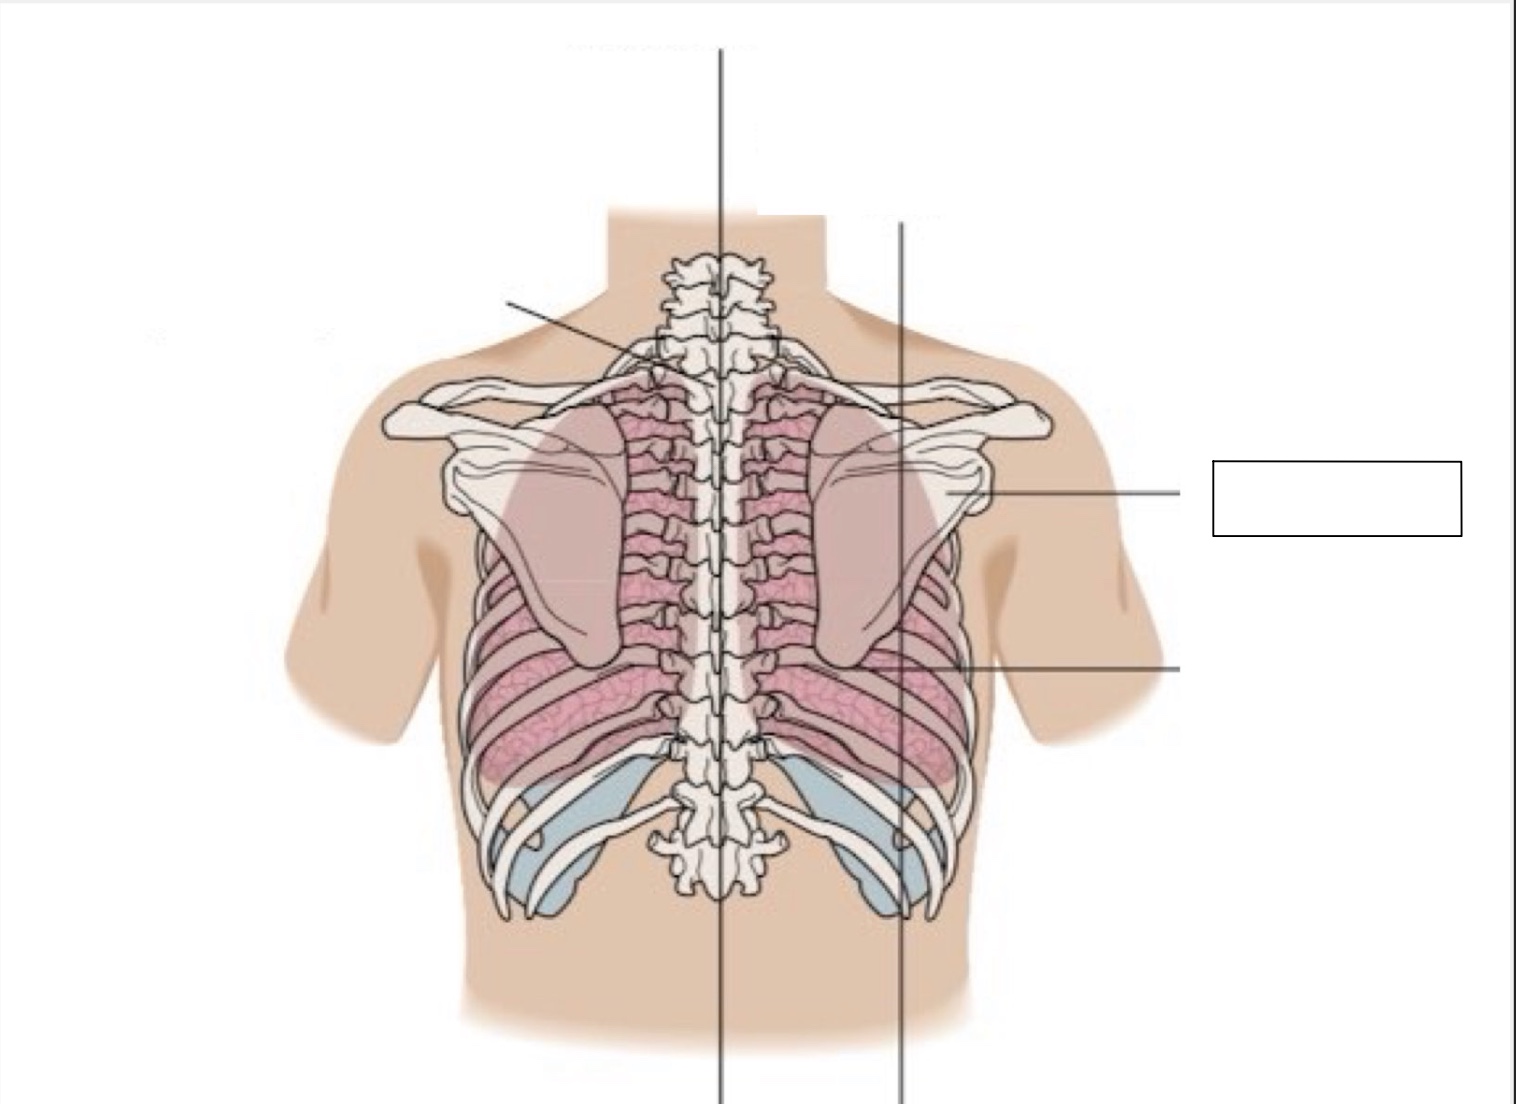

inferior angle of scapula

scapula

midscapular line

midspinal line

spinous process